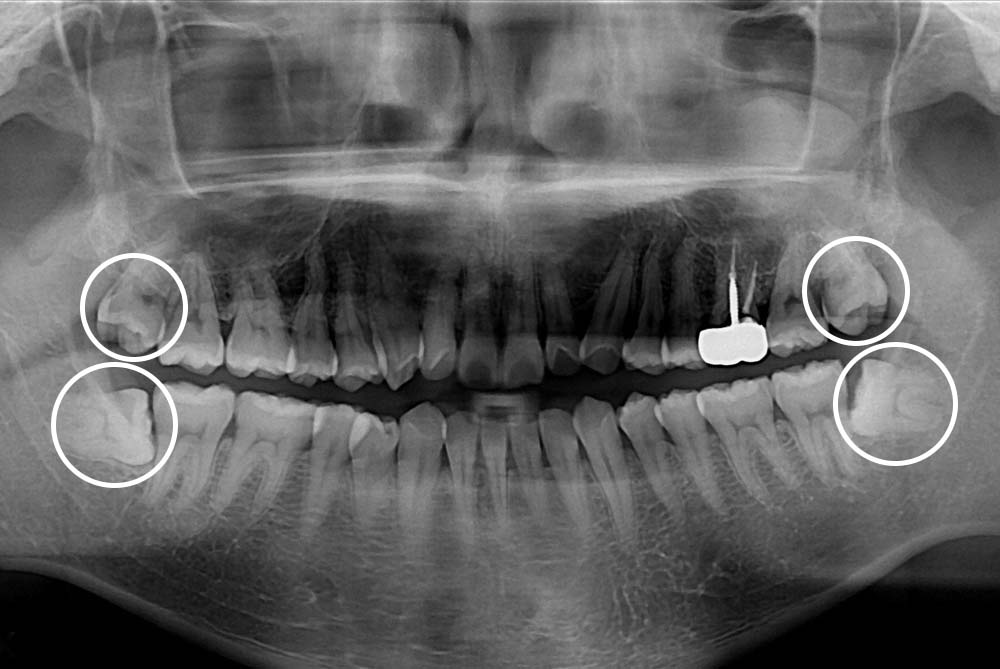

[사랑니] 매복 사랑니 발치

치료후 : 2019-04-10